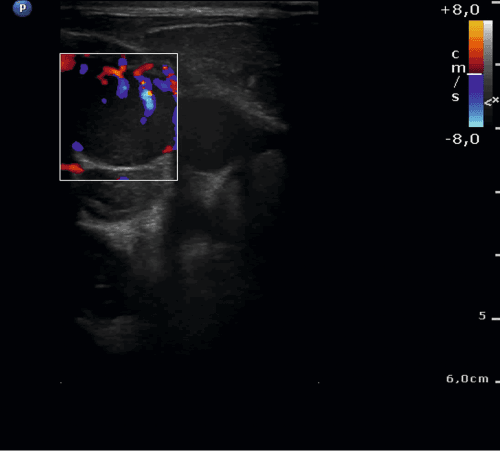

Chłopiec niespełna 16-letni zgłosił się do izby przyjęć z powodu bólu i obrzęku szyi po stronie lewej. Dwa tygodnie wcześniej dziecko przebyło infekcję dróg oddechowych z kaszlem, bez gorączki. Dodatkowo od około tygodnia chłopiec skarżył się na poty nocne. Przy przyjęciu stan ogólny dziecka był dobry, w badaniu fizykalnym z odchyleń od normy: obrzęk szyi, bolesność uciskowa po stronie lewej; ruchomość szyi zachowana. Stwierdzono liczne, drobne węzły chłonne szyjne oraz obecne znacznie powiększone węzły limfatyczne nadobojczykowe i podobojczykowe po stronie prawej. W badaniach laboratoryjnych podwyższona wartość OB. W rtg klatki piersiowej uwidoczniono poszerzenie cienia śródpiersia przedniego. W wykonanym badaniu USG na szyi głównie po stronie prawej i nadobojczykowo zobrazowano liczne węzły chłonne o znacznie zmienionej morfologii, hipoechogeniczne lub o mieszanej echogeniczności, ze słabo widoczną wnęką i wzmożonym unaczynieniem. W pomiarach: węzły nadobojczykowe po stronie prawej wielkości 32 x 9 mm, kolejny 22 x 14 mm (z możliwymi cechami rozpadu), kilka węzłów do 13 mm widocznych było częściowo zamostkowo (najprawdopodobniej w śródpiersiu); po stronie lewej nadobojczykowo obecne były liczne, drobne, hipoechogeniczne węzły chłonne. Unaczynienie węzłów limfatycznych było chaotyczne, zobrazowano naczynia wnikające z obwodu. Dodatkowo uwidoczniono zakrzepicę żyły szyjnej wewnętrznej prawej. Zdecydowano o chirurgicznym usunięciu jednego z węzłów chłonnych. Istotny jest fakt, że do badań histopatologicznych u dzieci pobiera się cały węzeł chłonny. Nie wykonuje się biopsji cienkoigłowej z uwagi na znaczny odsetek niediagnostycznych wyników. Na podstawie badania hist-pat rozpoznano chłoniaka Hodgina i rozpoczęto leczenie onkologiczne.